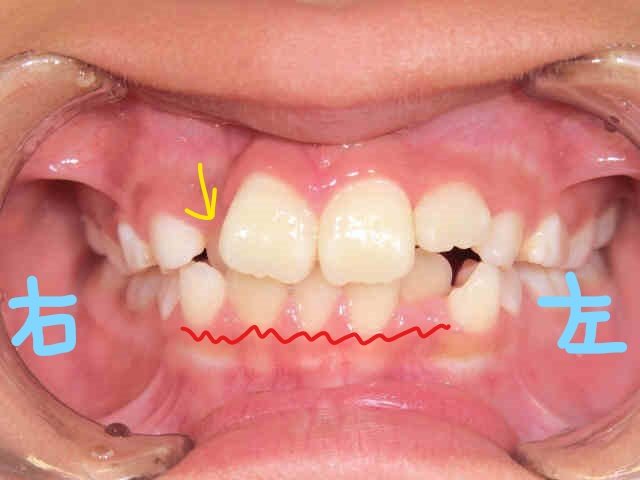

左上の写真は正面から、右上は下から見上げた角度の口腔内写真です。初診時には内側に位置していた右上前歯(黄色矢印の歯)が、上顎歯列の拡大によって前方に誘導されている様子が確認できます。また、下顎前歯(赤色波線部分)の叢生(いわゆるガタガタの歯並び)にも改善傾向が見られます。

とはいえ、下顎の叢生が整い始めていることは、治療の進行として望ましい兆しといえるでしょう。一般的に、下顎の歯列調整は上顎よりも難しいとされており、この段階での改善は非常に前向きな変化と考えられます。